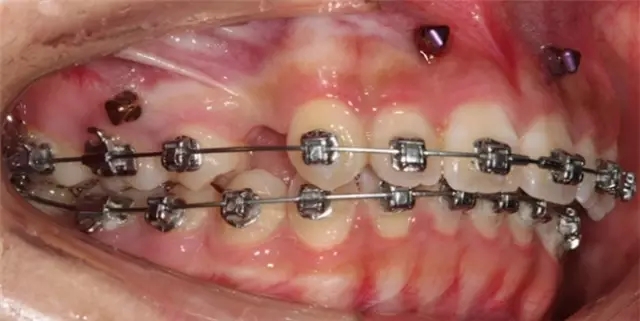

Damon 病例分享:安氏 II 類(lèi)二分類(lèi)露齦笑的矯治(董一磊)

患者信息

治療前后對(duì)比